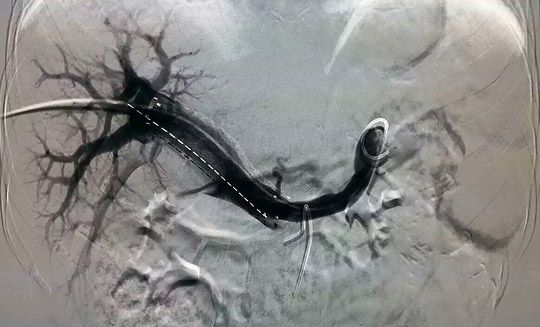

—腫瘤一科成功開展山東省首例支架+碘125粒子條治療門靜脈主干癌栓

2015年11月27日,在復旦大學附屬中山醫(yī)院介入科羅建鈞教授指導下,腫瘤一科張開賢主任帶領吳林霖、邢超、楊森等年輕醫(yī)生組成的介入團隊,成功地對一例原發(fā)性肝癌并門靜脈主干癌栓的患者實施了山東省首例支架+碘125-粒子條+肝動脈栓塞化療術,術后患者情況良好,目前正在進一步康復中。

門靜脈癌栓治療方法眾多,其中支架+碘125粒子條植入是近年來應用的一種新方法。支架可迅速開通門靜脈,恢復向肝血流,緩解門靜脈高壓,使肝功能恢復正常,但普通支架由于只有機械擴張作用而沒有抗腫瘤作用,術后很容易導致門靜脈堵塞,為解決這一難題,在植入門靜脈支架的同時植入碘125-粒子條,利用碘125放射性粒子發(fā)出的低能量伽馬射線持續(xù)殺傷腫瘤細胞,有效控制腫瘤生長,防止門靜脈再次堵塞,預防或推遲門靜脈再狹窄的發(fā)生,使門靜脈長時間保持通暢,為后續(xù)栓塞化療、消融治療等贏得時間,從而延長肝癌患者的生存期。